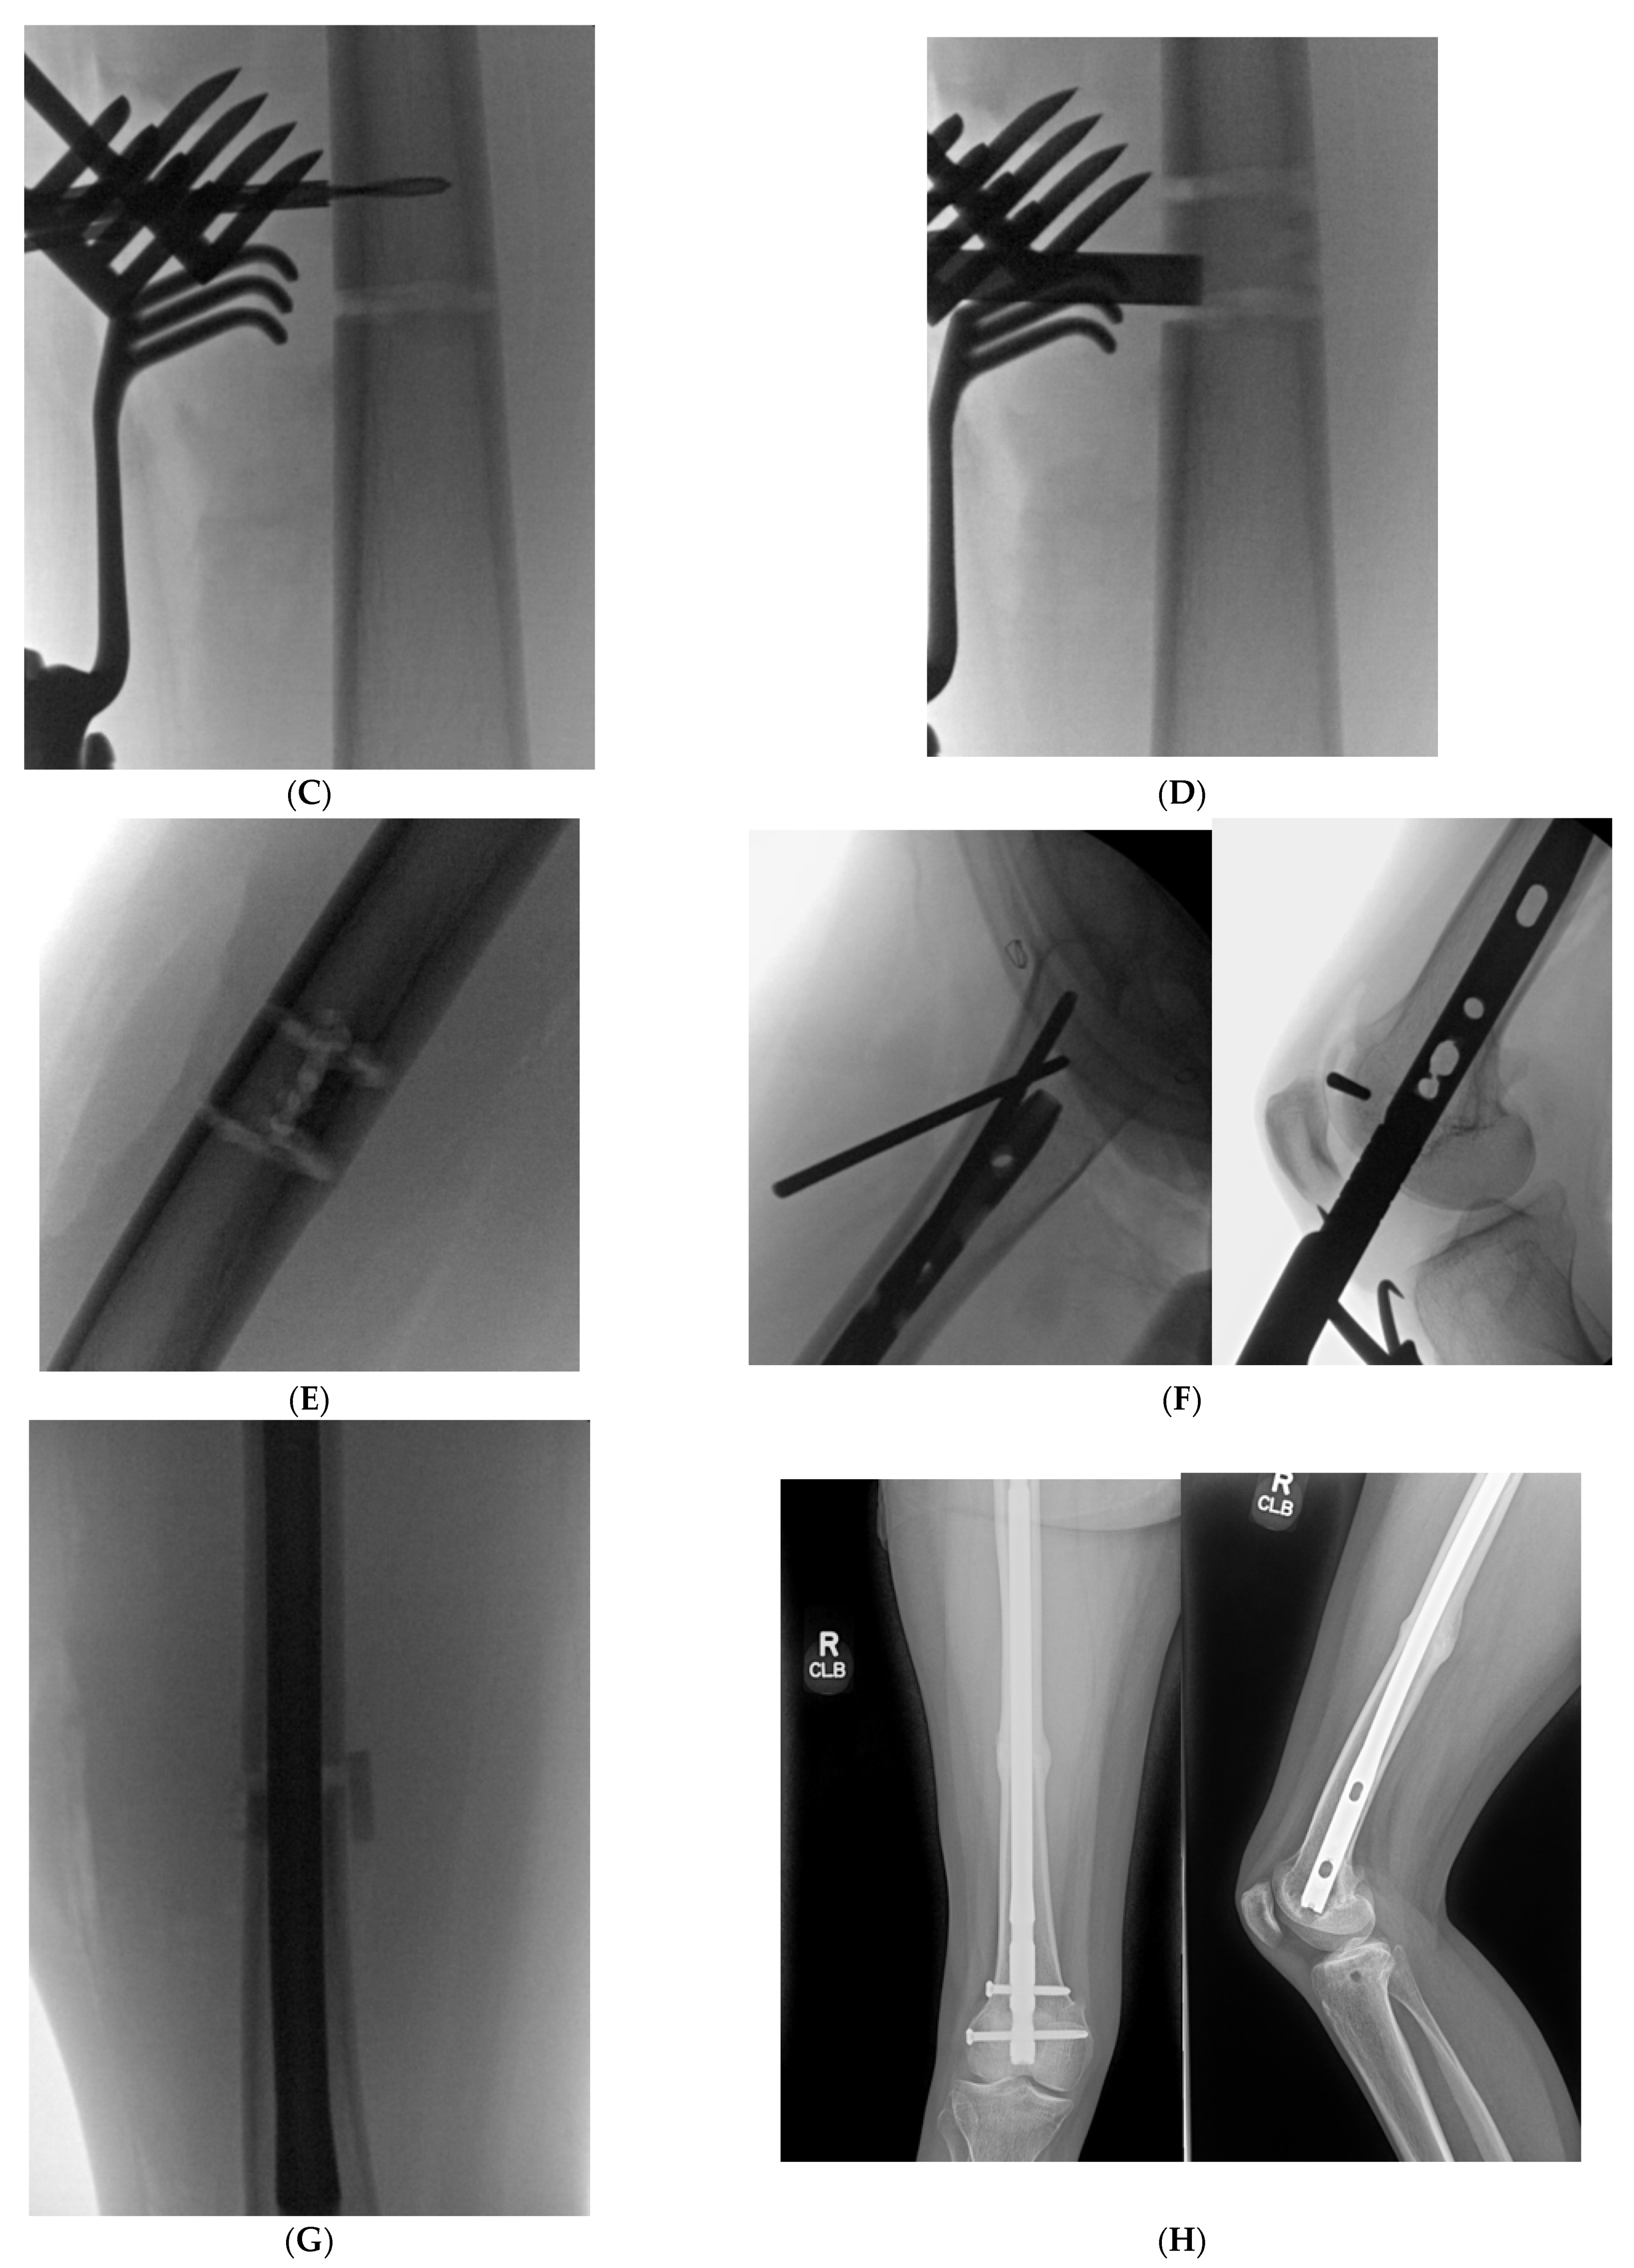

Figure 4. (A): Full length standing radiographs illustrating a left tibia diaphyseal malunion. (B): AP and lateral of tibia showing a diaphyseal malunion. (C): Intraoperative fluoro demonstrating bicortical drill holes parallel to medial face of the tibia. This is prior to the utilization of the osteotome and the perpendicular saw cut. Remember to remove retractors prior to the reaming process. (D): Intraoperative fluoro illustrating the clamshell osteotomy. Notice secondary fracture line propagated during the osteotomy (red arrow). (E): The reamer was pushed pass the osteotomy zone during the reaming process. This is to prevent iatrogenic injury to neurovascular structures. (F): AP and lateral fluoroscopic images demonstrating improved alignment after clamshell osteotomy and implantation of intramedullary nail. Poller screws may be required to assist with reduction. However, the poller screw in this scenario was inserted for definitive fixation to prevent any endosteal motion of intramedullary nail. (G): AP and lateral XR demonstrating osseous union at 3 month follow up.

An elderly male presented to clinic with an obvious deformity to his left leg with a chronic history of left knee and ankle pain. He sustained a fracture of the proximal third of the tibial diaphysis approximately 7 years prior that was managed non-operatively in a long leg cast. He subsequently developed a posttraumatic tibial varus deformity with severe tricompartmental knee arthritis. His primary complaints were abnormal gait pattern, and severe functional knee pain. Physical examination was significant for tibial shortening, genu varus, and internal tibial torsion. Full-length radiographs revealed medial mechanical axis deviation. His medial proximal tibial angle measured 78° and the apex of angulation at center of rotation of angulation measured 14°. Total knee arthroplasty was not an option secondary to his severe extra-articular deformity that could predispose to early implant failure. Thus, deformity correction was undertaken with a clamshell osteotomy (Figure 4). A posteromedial approach was used to expose the malunited segment. In follow up care, wound dehiscence of the posteromedial approach was noted, requiring local wound care and oral antibiotics. Eventually, he healed his osteotomy uneventfully, and was able to obtain a total knee arthroplasty.